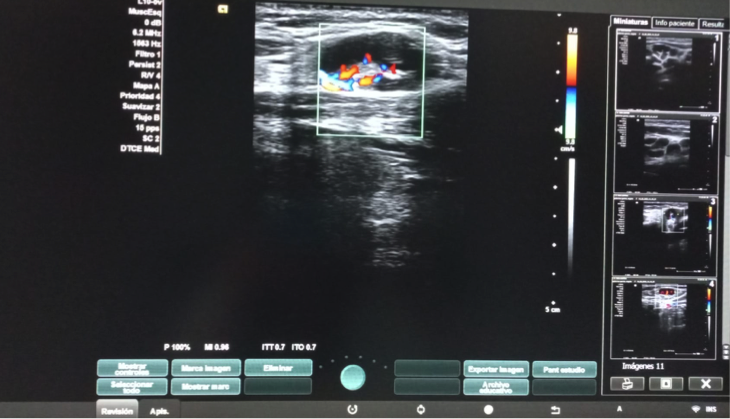

Hallazgos ecográficos

Dos adenopatías en territorio laterocervical derecho, con hilio central y doppler positivo, alguna con diámetro transversal superior al longitudinal, de probable origen reactivo y una adenopatía supraclavicular sin hilio central y con vascularización generalizada.